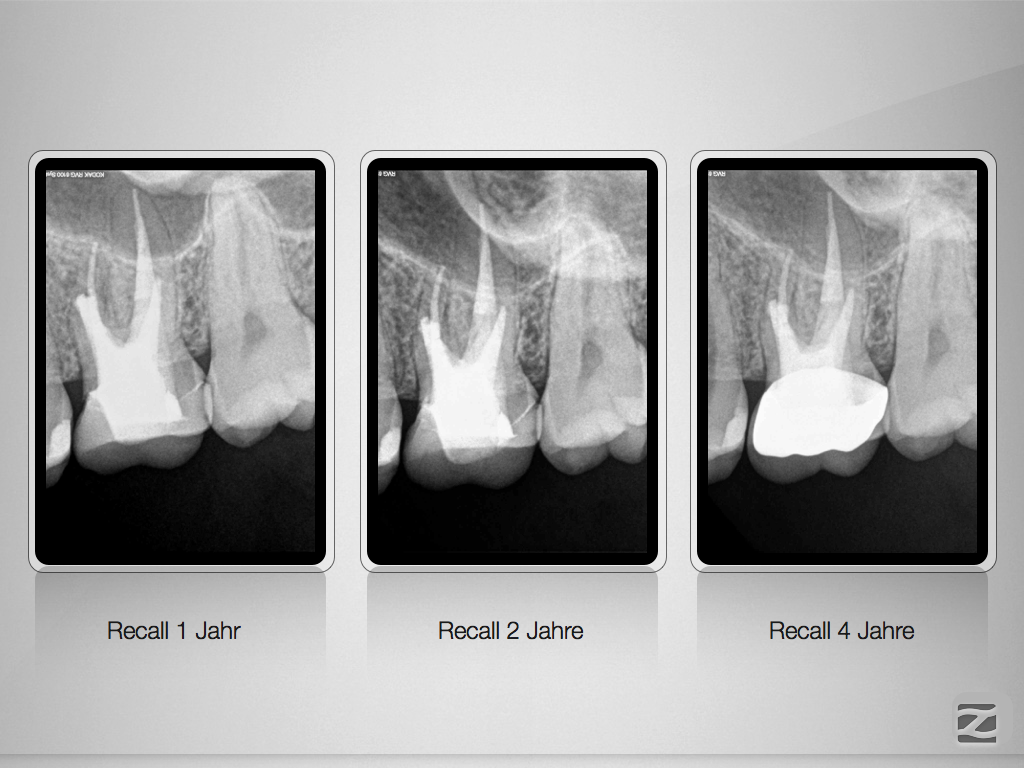

26 Recall 4 Jahre.006 Veröffentlicht 16. Juli 2015 am 1024 × 768 in Wie hoch ist eigentlich die Recall-Rate?